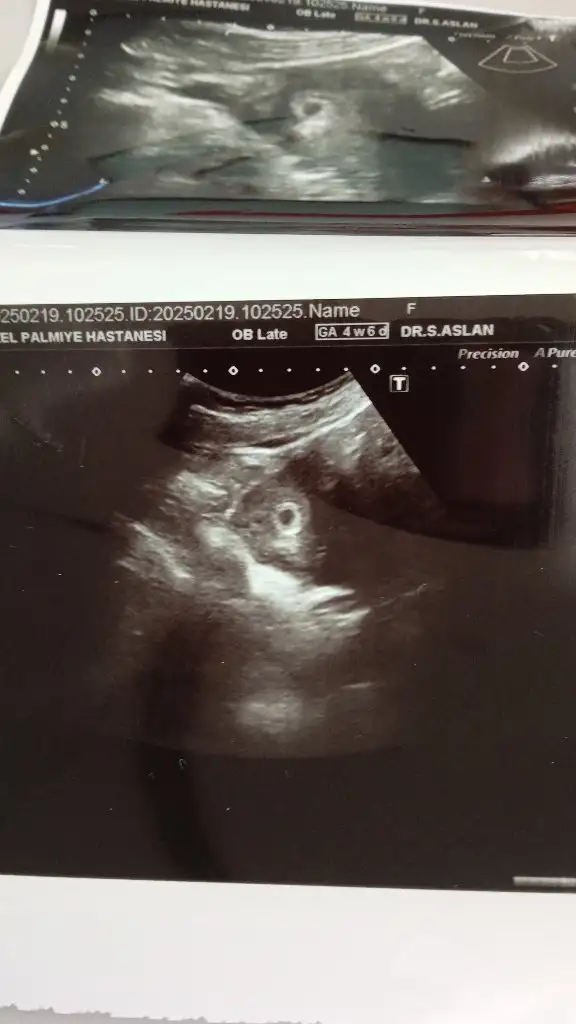

Biz bu gün bebişimizi gördük 5 haftalığız. Dilerim isteyen anne olmayı hak eden herkesin hepinizin başına inşallah